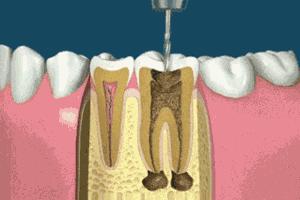

一般情况下,我们牙齿的蛀牙会经历这几个过程:大家看下图↓↓↓

一般情况下到了深龋,并伴有疼痛,说明蛀牙已经影响到牙髓腔了,如果牙髓被感染了就要进行根管治疗。并不是医生想要唬你。如果还没到达深龋,没有感染牙神经,一般只需要进行去腐后常规补牙即可。